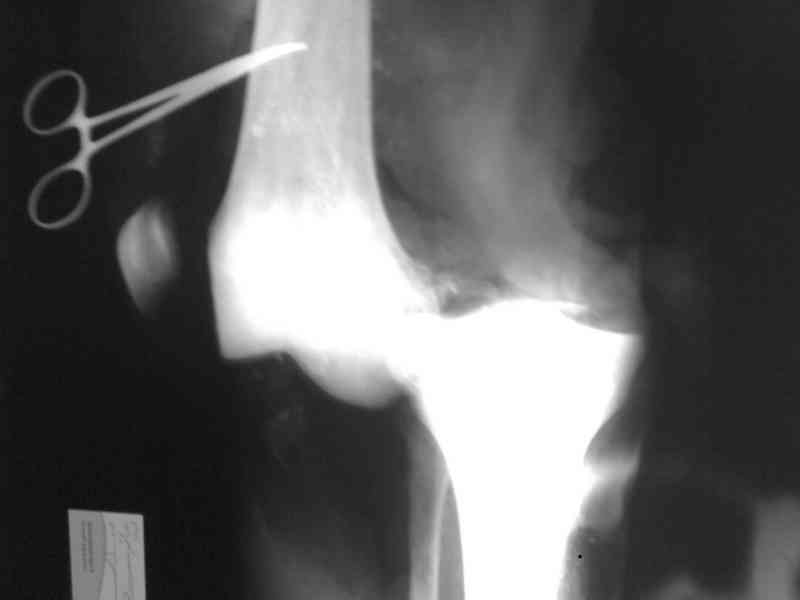

Снимки прошлых публикации из моего Power point

На ренгенограмме хорошая аппозиция костей коленного сустава, но надколенник находится подозрительно высоко, поэтому необходимо убедиться в отсутствии повреждения связки надколенника.

Наличие пульсации на конечностях еще не доказательство отсутствия интимальных повреждении сосудов, наблюдались вторичные осложнениия, поэтому важна консультация сосудистого специалиста.

Аппарат внешней фиксации удаляется в 6-7 недель,

предпочтительно под общим обезболиванием, во время

удаления проверяется стабильность и амплитуда движения в коленном суставе с редрессацией.